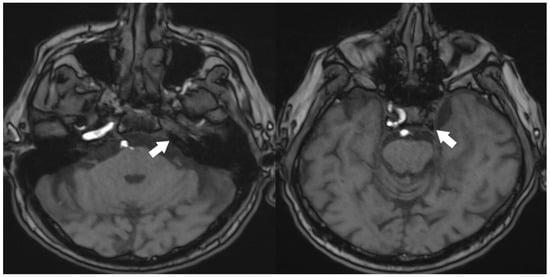

A 70-year-old male patient has presented with ongoing complaints of headache [VAS scale 6], pulsatile tinnitus [TFI level 3], and occasional dizziness. Neurological examination has revealed intact cranial nerves, bilaterally normal cerebellar function, normal deep tendon reflexes, a negative Romberg test, and preserved muscle strength. No abnormalities have been detected in other systemic examinations. Laboratory investigations showed no remarkable abnormalities. However, prior laboratory records indicated dyslipidemia for which the patient was under treatment, and he also had a known history of primary hypertension. Cranial MRI and MR angiography have demonstrated an absence of flow in the left internal carotid artery (Figure 1 and Figure 2).

Figure 2.

TOF 3D imaging of cranial MRI angiography [White arrow: no contrast filling in the carotid artery].